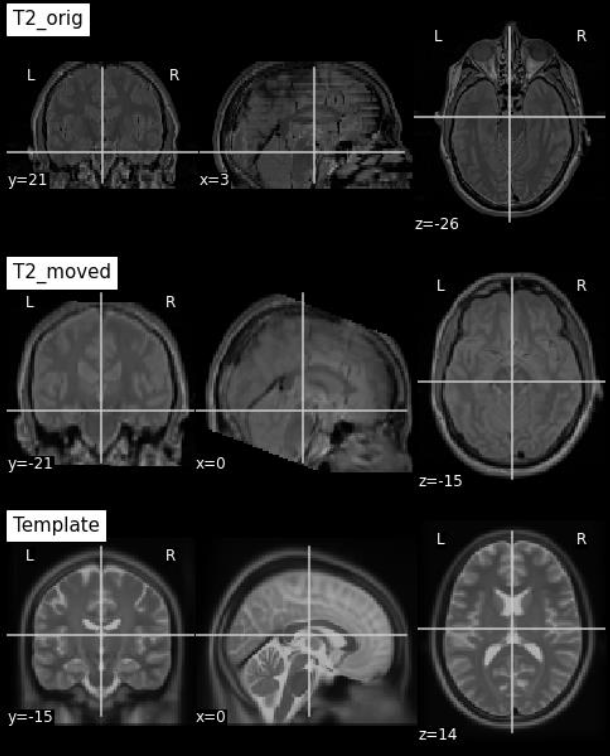

Image Registration

The image registration process consists of combining two images by superimposing one image to the other [47]. In the medical field, image registration allows you to combine data from multiple modalities to obtain comprehensive patient information: it can help monitor tumour growth, facilitate treatment verification, improve interventions, or compare patient data with a template. To apply image registration we need a starting image, a registration algorithm, and a target image, in our case a template. A template is an MRI in a particular spatial location (see Fig. 6 as an example). Model building is an iterative process that involves normalizing, aligning, and averaging an MRI set from different patients [23]. Templates serve as a common reference space and allow researchers to combine and compare data from multiple people and play an important role in a variety of neuroimaging activities:

Through the FLIRT 222https://fsl.fmrib.ox.ac.uk/fsl/fslwiki/FLIRT tool, image registration was applied using the templates available on TemplateFlow [44], as shown in Fig. 7.

Figure 7: Image registration.